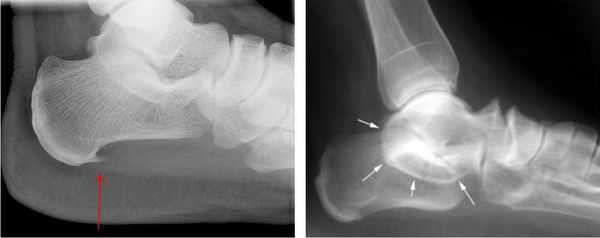

При подозрении травматической природы синдрома проводится рентгенография голеностопного сустава и стопы. Во время исследования также можно обнаружить костные выступы и остеофиты.

Рис 2. Иррадиация болевых ощущений при наличии синдрома тарзального канала.

При этом, рентгенографические исследования (МРТ, КТ, УЗИ) стопных отделов под нагрузкой, позволяют выявить наличие/отсутствие различных деформационных изменений, остеофитов, переломов, а также иных видов проблем, провоцирующих изменение нормальной формы канала предплюсны.

Как правило, рентген помогает специалисту получить оптимально корректную информацию и, на ее основе, применить наиболее эффективную тактику лечения - консервативную, либо хирургическую.